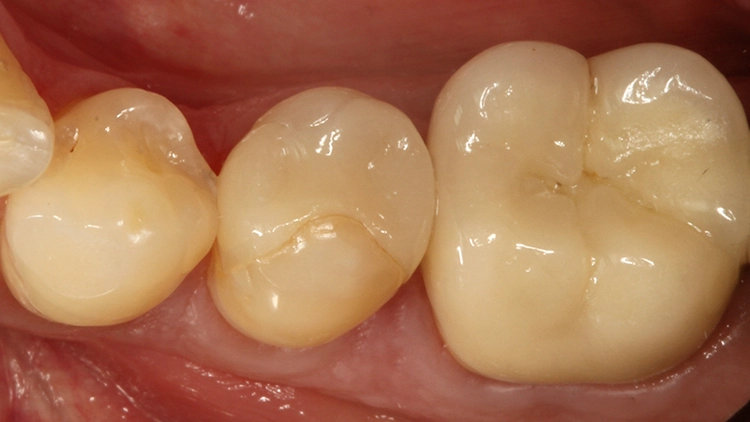

Der 55-jährige Patient störte sich an dem Randausbruch seines erst 10 Jahre alten Keramikinlays an Zahn 45 (Abb. 7). Er wünschte eine Neuversorgung mit Keramik. Nach eingehender Aufklärung und Beratung konnte er davon überzeugt werden, dass in der Dimension der Kavität eine direkte Kompositversorgung genauso funktionieren könnte.

Der sehr anspruchsvolle Patient haderte zunächst wegen der Ästhetik von „Kunststofffüllungen“: Er war der Überzeugung, dass hier keine adäquate Farbanpassung möglich sei, ließ sich aber auf den Vorschlag der direkten Kompositversorgung ein. Dieser Fall sollte dann eine Challenge für die Universalfarbe Venus Diamond One werden – aufgrund vorangegangener guter Erfahrungen von über 1,5 Jahren mit dem Material [10] konnte man sich ziemlich sicher sein, dass hier automatisch eine adäquate Farbanpassung stattfinden wird und gar keine hochspezifische individuelle Zahnfarbbestimmung erforderlich ist.